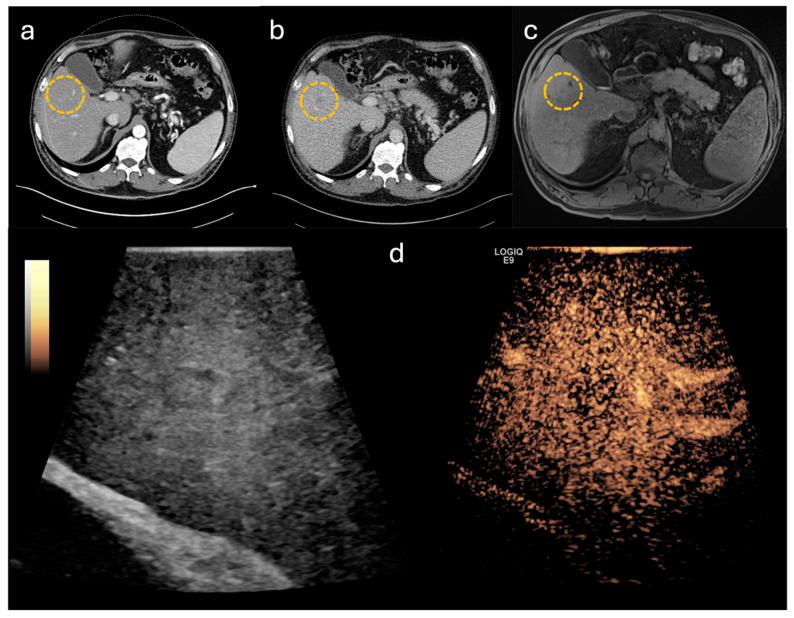

The aim of this study was to evaluate the performance and the impact of contrast-enhanced intraoperative ultrasound (CE-IOUS) on intraoperative decision-making, as there is still no standardized protocol for its use. Therefore, we retrospectively analyzed multiple CE-IOUS performed in hepato-pancreatic-biliary surgery with respect to pre- and postoperative imaging and histopathological findings.

Data of 50 patients who underwent hepato-pancreatic-biliary surgery between 03/2022 and 03/2024 were retrospectively collected. CE-IOUS was performed with a linear 6-9 MHz multifrequency probe connected to a high-resolution device. The ultrasound contrast agent used was a stabilized aqueous suspension of sulphur hexafluoride microbubbles.

In total, all 50 lesions indicated for surgery were correctly identified. In 30 cases, CE-IOUS was used to localize the primary lesion and to define the resection margins. In the remaining 20 cases, CE-IOUS identified an additional lesion. Fifteen of these findings were identified as malignant. In eight of these cases, the additional malignant lesion was subsequently resected. In the remaining seven cases, CE-IOUS again revealed an inoperable situation. In summary, CE-IOUS diagnostics resulted in a high correct classification rate of 95.7%, with positive and negative predictive values of 95.2% and 100.0%, respectively.

CE-IOUS shows excellent performance in describing intraoperative findings in hepato-pancreatic-biliary surgery, leading to a substantial impact on intraoperative decision-making.